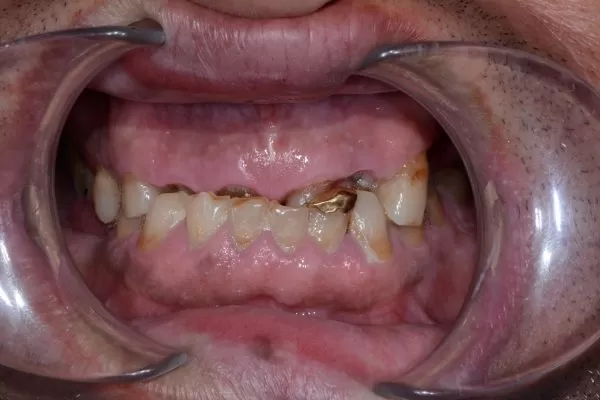

– Các răng bị mòn và ê buốt, thậm chí nứt, gãy.

Điều trị chỉnh nha hoặc điều chỉnh các răng gây cộm khớp, thay các răng giả mới để giúp bạn có được khớp cắn tốt. Đối với các trường hợp mòn răng nhiều gây sụp khớp, cần làm phục hồi toàn hàm (bằng mão sứ) để tái tạo lại kích thước dọc.